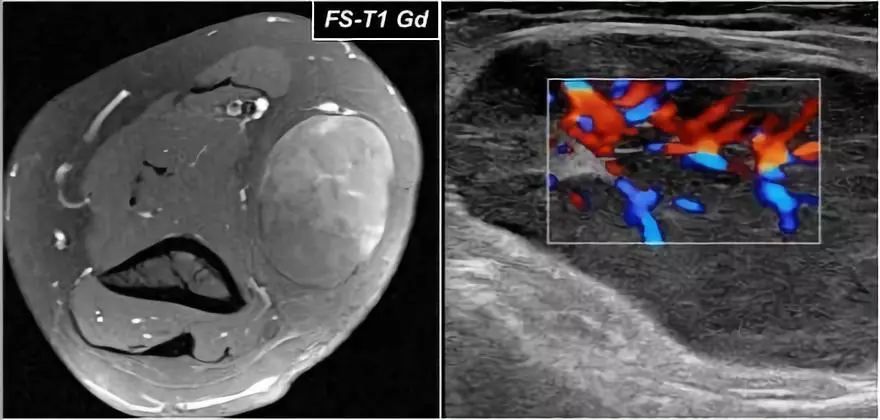

下面里一个26岁的女性,在滑车上区域的肿块的图像。它看起来非常均匀的囊肿。

增强扫描后,注意到矢状超声图像上MRI的不均匀增强和突出的内部血管分布。

所以这不是一个囊性肿块。再次被诊断为不确定包块。活组织检查的最终诊断是淋巴瘤。